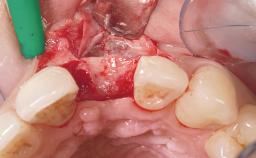

Immediate Flapless Placement of an Implant in a Maxillary Left Central Incisor Site

A 29-year-old female patient presented for treatment to replace the upper left central incisor tooth with an implant- supported restoration. The tooth had been intermittently symptomatic for the previous 12 months. The tooth had originally suffered trauma about 15 years previously. Several endodontic treatments had been performed, including an apicectomy procedure to retain the tooth. The patient was healthy and a non-smoker. She had reasonable expectations in regard to esthetic outcomes and the risk of marginal tissue recession following treatment. At medium smile, the gingival margins of the upper teeth were visible, with a display of 3 to 4 mm of the gingival margins. Gingival recession of tooth 21 and a discrepancy in the gingival levels between teeth 11 and 21 was observable during normal speech and smile.

Soft Tissue Contour and Volume Slightly compromised